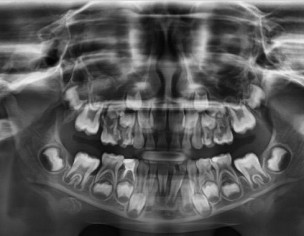

My daughter is 7 and hav deep cavity I took her to dentist one said she need 1 extraction and when I went to pediatric dentist she said she needs 4 extractions which she is going to do altogether same day I am attaching her xrays can any dentist plz advise after looking at the xrays thanks

Her both upper D are definitely for extraction and for her E need to evaluate clinically as well there might get b some Endodontic treatment and space maintainers afterwards

After extraction she will need space maintainer to keep first molar in its place so better to go for RCT to keep this tooth till age 12

can be done in two to three settings . even single extraction and space maintainers can be provided.